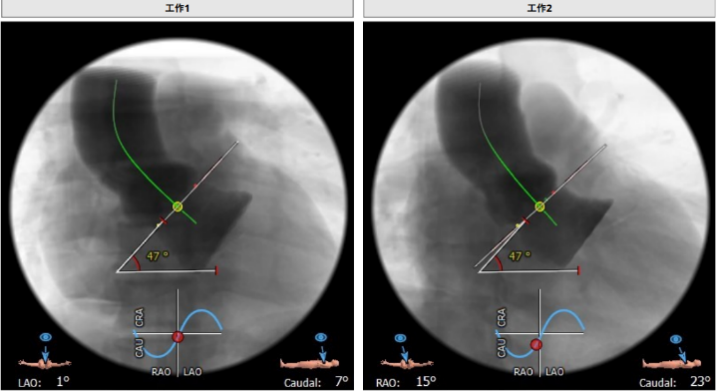

心脏角度:47°,升主动脉40mm:35.3mm

释放体位:LAO:1°,CRA:7°左冠线切位:LAO:10°,CRA:3°